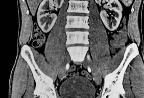

2. 복부 CT로 어떤 걸 볼 수 있나요?

복부 CT는 아래와 같은 광범위한 장기와 구조물을 확인할 수 있어요.

관찰 가능한 장기 진단 가능한 질환

| 간 | 지방간, 간염, 간암, 간낭종 |

| 담낭/담도 | 담석, 담낭염, 담도폐쇄 |

| 췌장 | 췌장염, 췌장암, 낭종 |

| 신장 | 결석, 수신증, 신장 종양 |

| 비장 | 비대, 손상, 낭종 |

| 위·장 | 장 폐색, 대장염, 게실염 |

| 복강혈관 | 대동맥류, 혈전 |

| 림프절 | 비대, 전이 가능성 |

| 여성 생식기 | 자궁, 난소 종양/낭종 등 (한정적) |

즉, 단순 복통부터 암 진단까지 다양한 목적에 활용되는 검사예요.